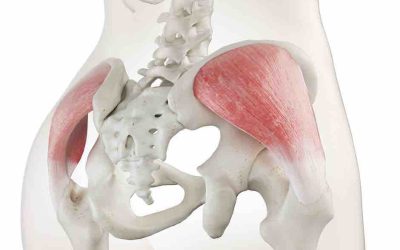

Síndrome del glúteo medio: causas, síntomas y tratamiento

El síndrome del glúteo medio es una afección dolorosa que afecta la región glútea. Se origina por la inflamación y lesiones en los tendones del músculo glúteo...